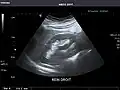

Abdominal Ultrasound (Full Exam)

STRUCTURED REPORT

(Technique: Transabdominal ultrasonography; Device: Toshiba Aplio XG)

Liver: Diffusely homogeneous and normal in echogenicity. No focal mass or contour nodularity. No intrahepatic biliary ductal dilatation.

Portal Vein: Patent main portal vein.

Gallbladder: No stones, wall thickening, or pericholecystic fluid.

Common Bile Duct: Nondilated measuring 1.3 mm at the level of the porta hepatis.

Pancreas: Visualized portions unremarkable.

Spleen: Normal in size.

Kidneys: Right and left kidneys measure 11.5 cm and 12 cm in length respectively. No hydronephrosis. Small left lower pole kidney cyst.

Ascites: None.

Aorta: Visualized portions normal in caliber, 16 x 15 mm.

IVC: Normal.

IMPRESSION:

Normal abdominal ultrasound.